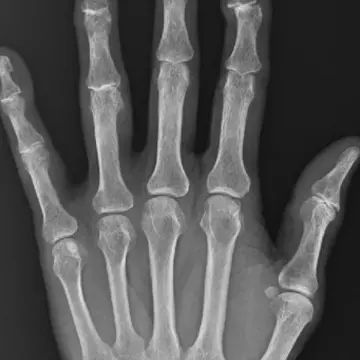

人さし指の第一関節にずれが生じることで曲がる

人さし指の第一関節にずれが生じることで曲がる。

『へバーデン結節』の炎症が進み、第一関節が曲がったケース

『へバーデン結節』の炎症が進み、第一関節が曲がったケース。